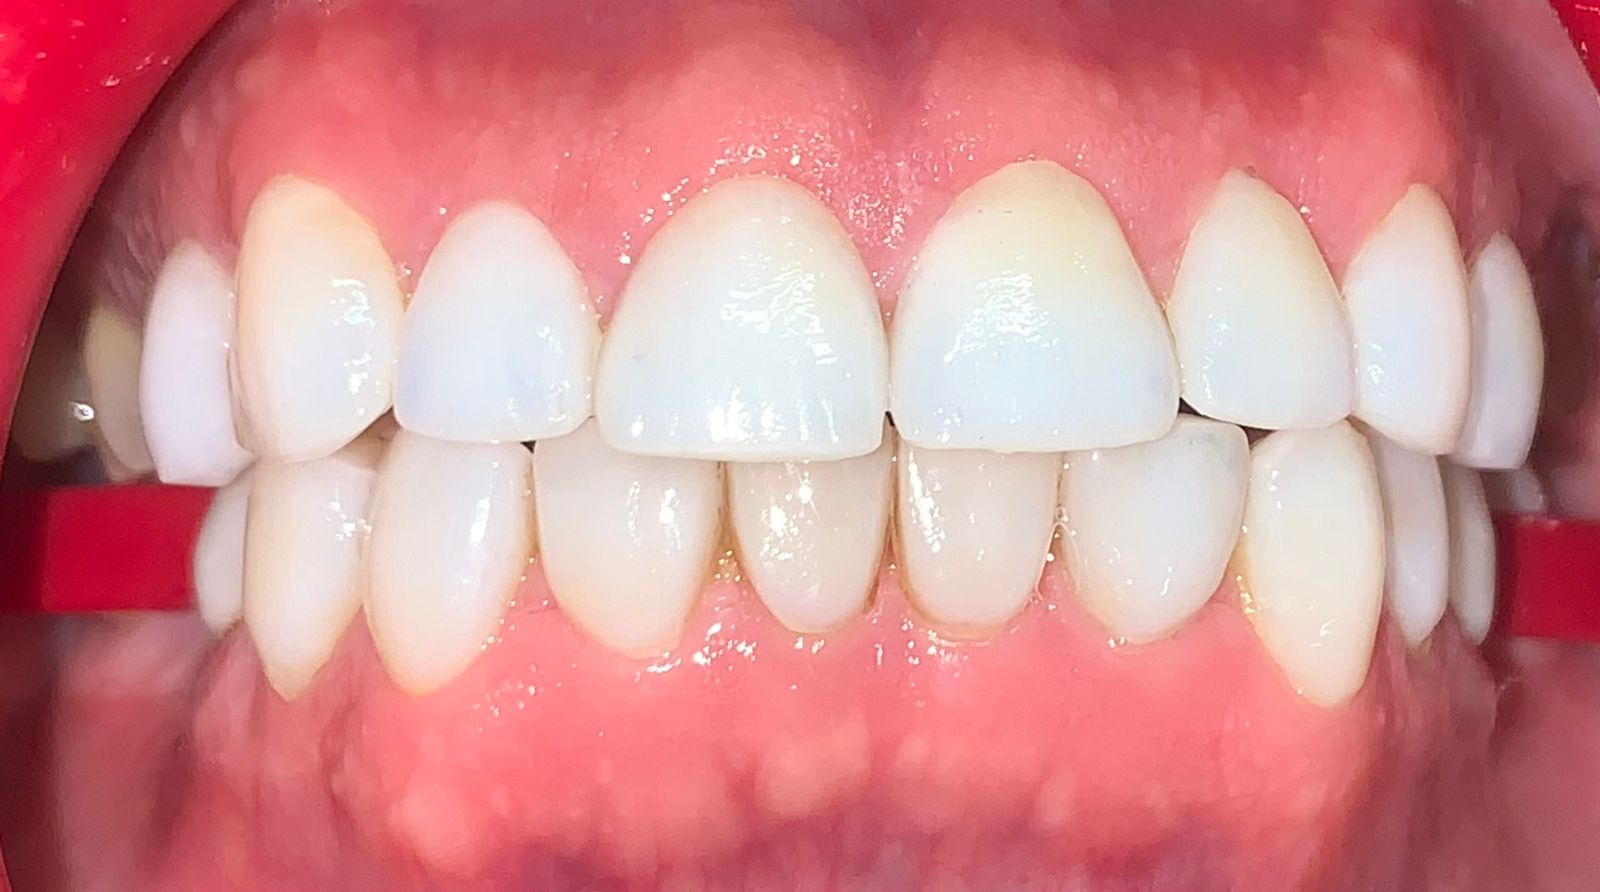

Fase 4: Resultado final de la rehabilitación oral completa

Fase 4

Rehabilitación Completa

Resultado final con prótesis fija e implantes dentales, restaurando función masticatoria, estética y calidad de vida del paciente.